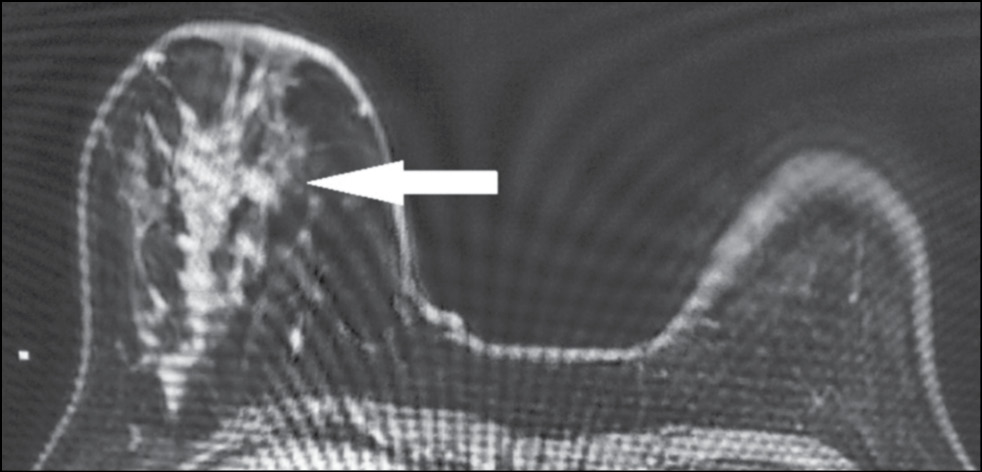

A 59-year-old patient complained of erosive changes in the nipple (Fig. 1). Physical examination revealed erythema, erosion, and nipple retraction. Doppler ultrasonography with color flow mapping revealed increased blood flow in the nipple projection (Fig. 2). Mammography findings were normal. To assess the extent of disease spread, breast MRI with contrast enhancement was performed. The early postcontrast series (Fig. 3) and maximum intensity projection (MIP) images (Fig. 4) showed a segmental contrast retroareolar area from the nipple level to posterior breast sections. Ultrasound-guided core biopsy followed by immunohistochemical analysis revealed Paget’s disease of the nipple with high-grade intraductal carcinoma in situ. Receptors for estrogen (G3 ER) and progesterone (PR) were negative. Oncogenic protein Ki-67 was 45%.

Figure 4. Magnetic resonance imaging of Paget’s disease (maximum intensity projection): the retroareolar area of segmental enhancement from the nipple level to the posterior breast (arrow).

In 22%–71% of cases, mammography provides a false-negative result [21], and in this case, breast MRI is indicated to identify abnormalities and deter the extent of disease spread. [20] Characteristic MRI findings include asymmetry, thickening, flattening, retraction of the NAC, and uneven contrast accumulation in this area. MRI allows evaluating adjacent structures and axillary lymph nodes.